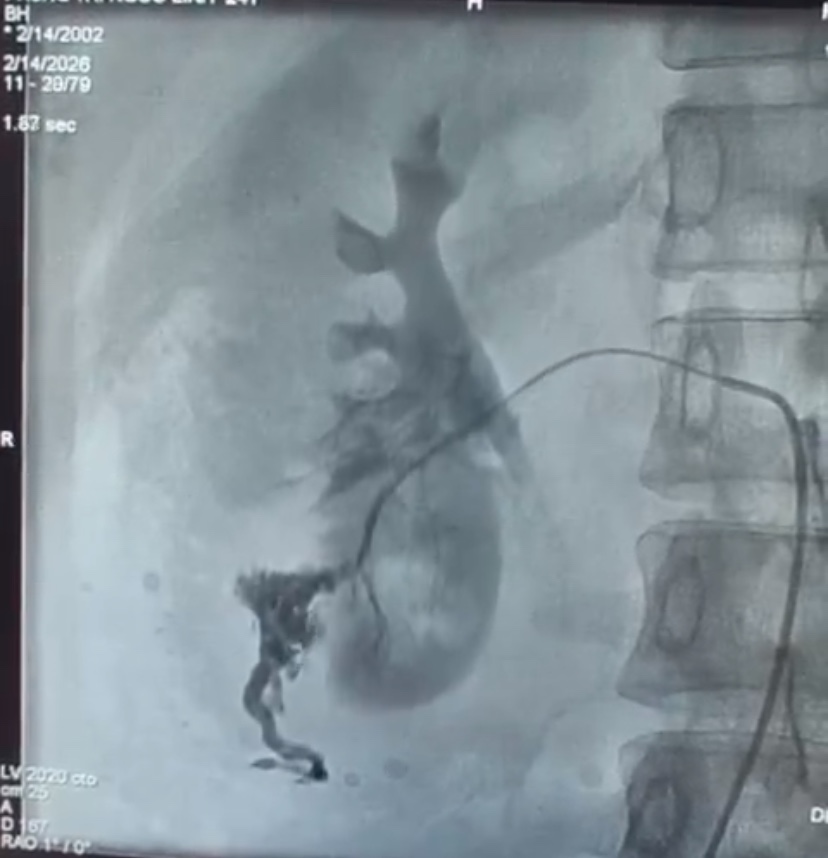

Ca can thiệp được ThS.BSCKII Lê Hồng Kỳ - trưởng khoa chẩn đoán hình ảnh và y học hạt nhân trực tiếp thực hiện. Trong quá trình can thiệp, chụp động mạch thận phải ghi nhận hình ảnh thoát thuốc từ các nhánh động mạch cực dưới. Bác sĩ tiến hành kỹ thuật siêu chọn lọc bằng microcatheter và nút mạch cầm máu bằng hỗn dịch Histoacryl – Lipiodol kết hợp Spongel.

Chụp kiểm tra sau nút mạch cho thấy các nhánh mạch tổn thương đã được tắc hoàn toàn, nhu mô thận còn lại được bảo tồn tốt. Thủ thuật diễn ra an toàn, không ghi nhận biến chứng trong và ngay sau can thiệp. Sau can thiệp, bệnh nhân được chuyển về theo dõi và điều trị tại khoa ngoại tiết niệu, hiện tình trạng bệnh nhân ổn định, tuy nhiên vẫn cần được theo dõi sát diễn biến bệnh.